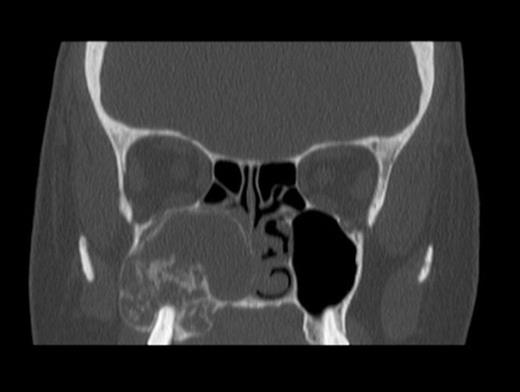

On clinical examination she was found to have complete nasal obstruction on the right side and bulging of the lateral nasal wall was noted. Intra-oral examination revealed buccal expansion of the upper right alveolar bone. A CT scan revealed a large right maxillary antral mass, with areas of radiolucency and radiopacity, extending into the right nasal cavity and ethmoidal air cells (Fig. 1). It appeared to contain flecks of calcification and was closely related to the maxillary molar teeth, however, root resorption and displacement of teeth were not features. A benign odontogenic tumour of the jaw was suspected.